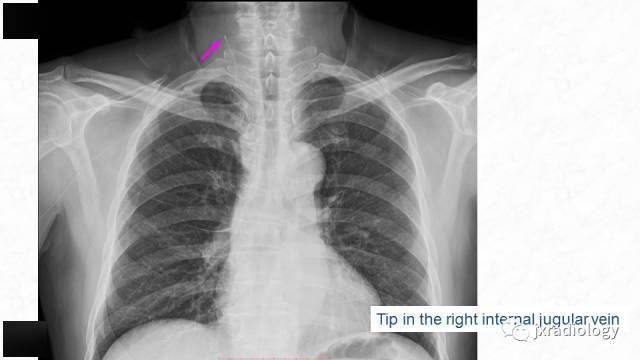

一例picc导管尖端移位于颈内静脉的处置对策

图片尺寸769x467